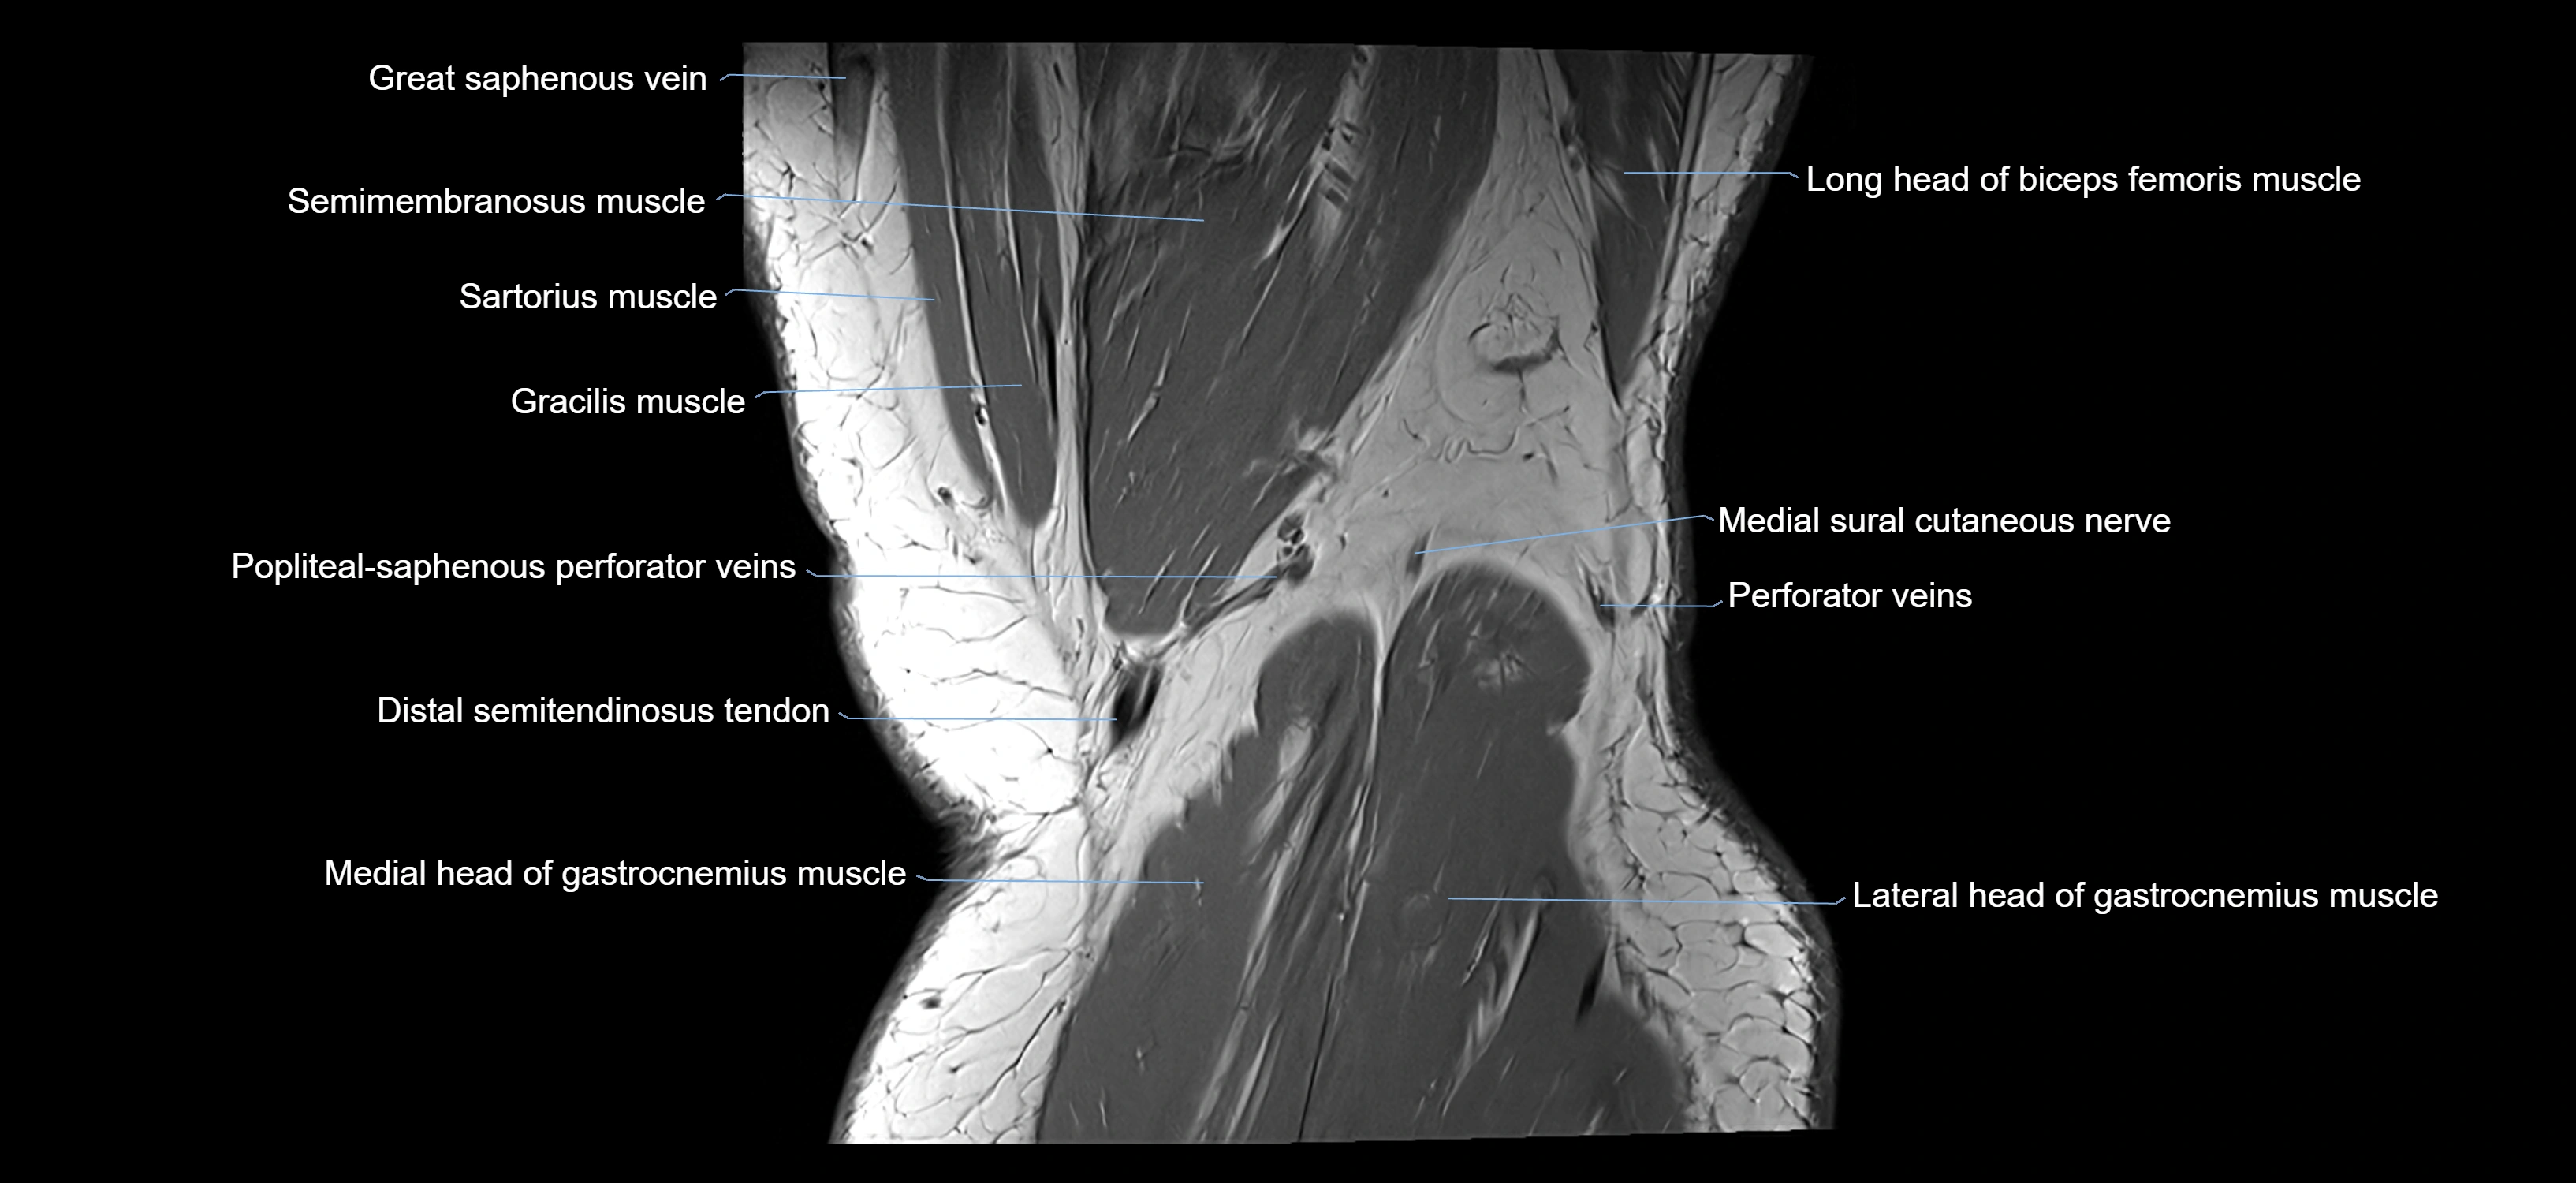

- Gracilis tendon (Distal)

- Medial head of gastrocnemius muscle

- Lateral head of gastrocnemius muscle

- Medial sural cutaneous nerve

- Popliteal–Saphenous perforating veins

- Sartorius muscle

- Semimembranosus muscle

- Semitendinosus muscle